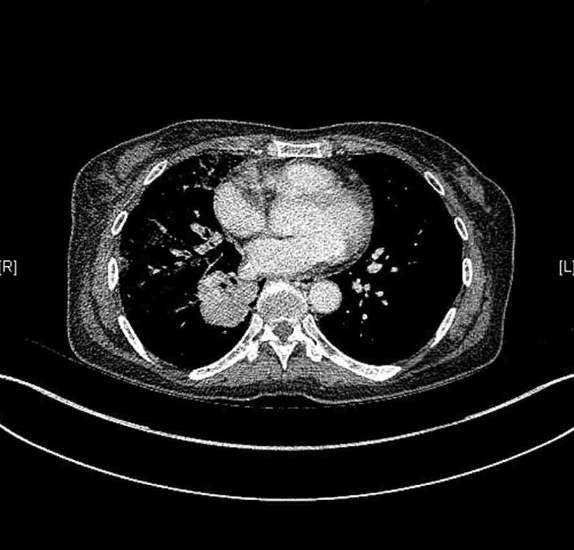

63세 여자가 2주 전부터 가래에 피가 묻어 나와서 병원에 왔다. 평소 계단을 오르면 숨이 찬다고 한다. 비흡연자이다. 혈압 110/70 mmHg, 맥박 80/분, 호흡 15회/분, 체온 36.5°C이다. 오른쪽 가슴에서 호흡음이 감소되어 들린다. 가슴 X선 사진과 가슴 컴퓨터단층촬영 사진이다. 혈액 검사 결과는 다음과 같다. 검사는?

CXR, CT: Irregular marginated mass involving RLL bronchus

• CXR 및 chest CT상 RLL bronchus를 침범하는 불규칙한 경계의 종괴가 관찰되며, 이는 폐암을 강하게 의심할 수 있는 소견이다.

• 확진을 위해 조직 생검이 필요하며, 종괴가 central airway와 인접해 있으므로 기관지경초음파 유도 기관지경유 조직검사(EBUS-TBNA)를 통해 적절한 검체를 확보해야 한다.